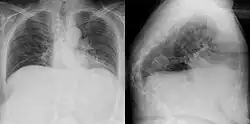

Gibbus deformity is a form of structural kyphosis typically found in the upper lumbar and lower thoracic vertebrae, where one or more adjacent vertebrae become wedged. Gibbus deformity most often develops in young children as a result of spinal tuberculosis and is the result of collapse of vertebral bodies.[1][2][3] This can in turn lead to spinal cord compression causing paraplegia.[4][5]

Gibbus deformity is included in a subset of structural kyphosis that is distinguished by a higher-degree angle in the spinal curve that is specific to these forms of kyphosis. Other conditions within this subset include Pott's disease and Scheuermann kyphosis, but gibbus deformity is marked by an especially sharp angle. Viewed from behind, the resulting hunchback is more easily seen when bending forward.[10] A kyphosis of >70° can be an indication of the need for surgery and these surgeries can be necessary for children as young as two years old, with a reported average of 8 years of age.[9]